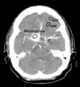

Intracranial meningioma

Meningioma, also known as meningeal tumor, is typically a slow-growing tumor that forms from the meninges, the membranous layers surrounding the brain and spinal cord. Symptoms depend on the location and occur as a result of the tumor pressing on nearby tissue. [Source: Wikipedia ]